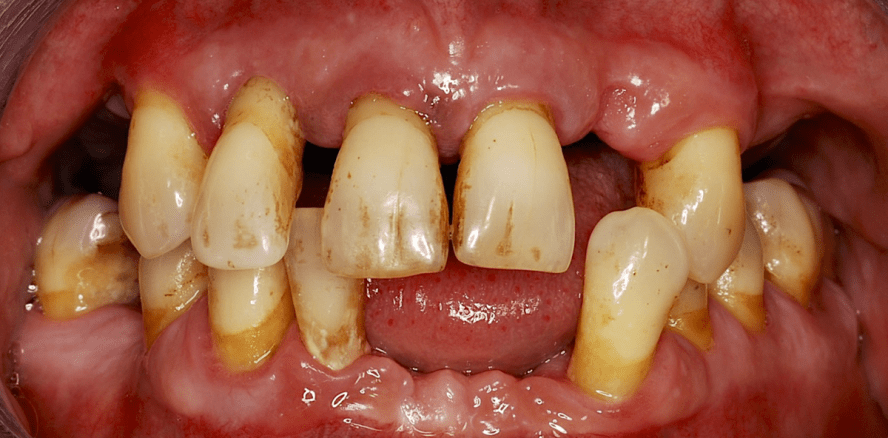

65-jährige Patientin mit positiver Raucheranamnese (generalisierte Parodontitis gravis et complicata). Aufgrund der parodontalen Erkrankung ist es bereits zu Zahnverlusten und somit zu einer deutlichen Einschränkung der Kaufunktion gekommen (a, b). Auch die Restbezahnung ist bereits deutlich kompromittiert; Knochenverlust bis fast an die Wurzelspitze (c) sowie durchgängiger Furkationsbefall an den unteren Molaren (d, e). (© Autorin)